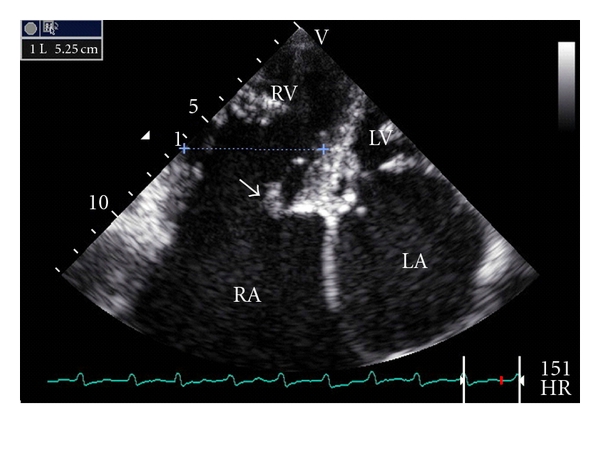

Transthoracic echocardiography showed a massive enlargement of the right atrium. The right atrial area was 80.6 cm² (53.7 cm²/m²), and the calculated right atrial volume was 621 mL (414 mL/m²); see Figure 2.

The right ventricle was dilated (52.5 mm, mild diameter, apical 4 chambers view, Figure 3). The tricuspid valve was not displaced but was thickened (Figure 3) with restrictive mobility in systole and no coaptation. There was a severe tricuspid regurgitation with a vena contracta width of 0.83 cm and a systolic reversal in hepatic vein flow.

In our case, the right atrial enlargement may be due to the severe pulmonary hypertension as a consequence of mitral stenosis and severe tricuspid regurgitation. Although we do not have surgical and pathological proof, we think that this regurgitation is a consequence of organic rheumatic tricuspid valve disease. This regurgitation might be also worsened by right ventricular dysfunction and dilatation, persistent pulmonary hypertension, and chronic atrial fibrillation. Mitral valve disease (mitral regurgitation more than mitral stenosis) also leads to giant left atrium [11]. The right atrium size was notably disproportionate to that of the left atrium (see Figure 2). In mitral stenosis, the occurrence of a giant right atrium and a nearly normal-sized or a moderate dilatation of the left atrium has been reported [12]. Calcification of the left atrial myocardium probably the result of organization of intra-atrial thrombus may prevent the left atrium from dilating [12]. In our case, we did not see any calcification in transthoracic echocardiography. Localized pericardial constriction or myocardial fibrosis in left atrium can also be suggested although in our case, we did not have any echocardiographic proof.